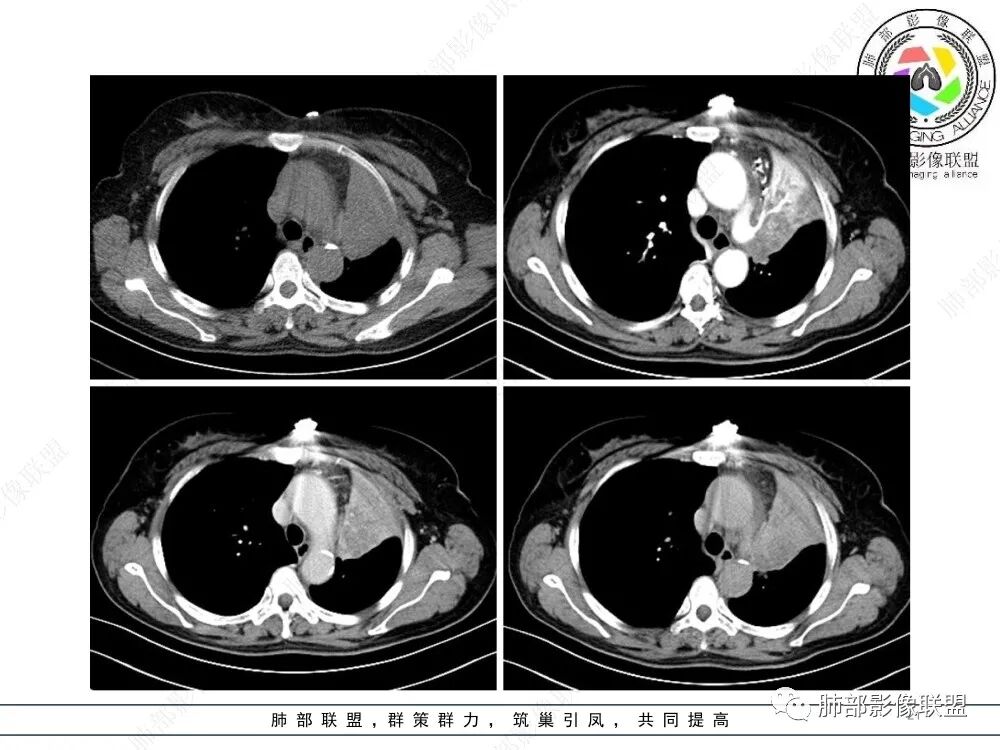

2、影像表现:正常肺背景,左肺上叶支气管腔内占位,上叶支气管截断,远端肺组织不张,强化差异衬托出肺门区结节影或块状影。增强扫描腔内占位轻中度不均匀强化,可见坏死,远端粘液栓,局部肺动脉受压、侵犯,纵膈淋巴结无明显肿大,无胸腔积液。

3、综合分析:老年女性,支气管腔内占位明确,病灶向周围侵犯,诊断恶性肿瘤并肺不张问题不大。需要考虑到的疾病谱有鳞癌、腺样囊性癌、粘液表皮样癌、类癌、小细胞肺癌等。